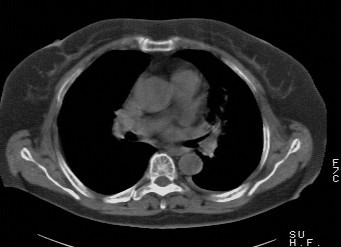

f,74发热咳嗽三天

考虑左肺上叶中央型肺癌并左肺上叶舌段肺不张。

考虑左肺上叶中央型肺癌并左肺上叶舌段肺不张.

左肺上叶舌段肺不张,建议作进一步检查除外中心型肺癌。

左肺上叶舌段肺不张,建议行纤支检查除外中心型肺癌。支持!